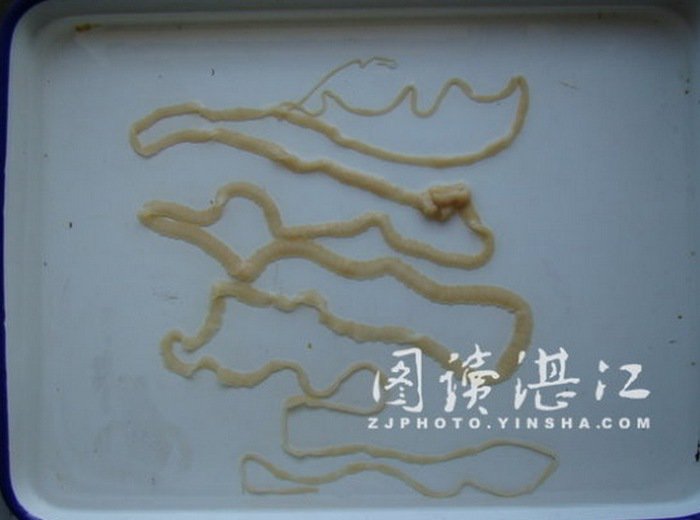

這名男子的體內全身上下竟都佈滿了縧蟲。縧蟲是寄生蟲的一種,主要寄居在宿主的腸子中,最長的縧蟲甚至能在宿主體內長至 15公尺。

很多時候縧蟲可以在宿主體內寄居好幾個月而不被發現,接下來就是在宿主身上產卵、繁衍下一代。如果沒有被檢查出來的話,縧蟲甚至可以在宿主體內存活數年

很多時候縧蟲可以在宿主體內寄居好幾個月而不被發現,接下來就是在宿主身上產卵、繁衍下一代。如果沒有被檢查出來的話,縧蟲甚至可以在宿主體內存活數年